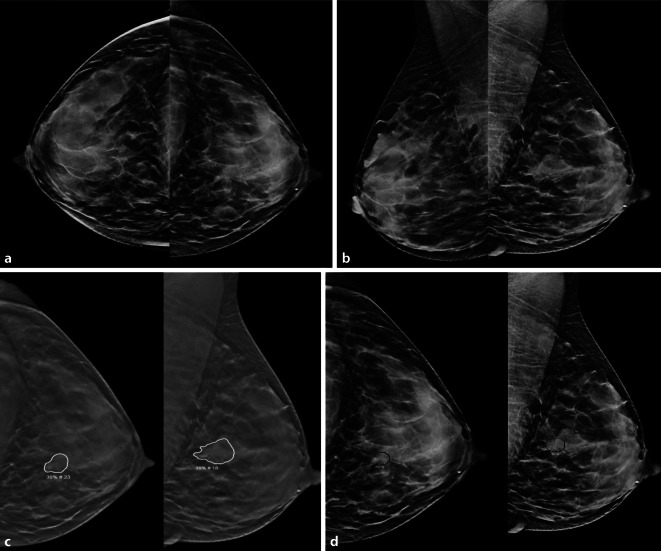

Standard radiological methods: In principle, AI applications are available for all imaging modalities, with a particular focus on mammography in breast diagnostics.

Methodical innovations: AI promises to filter examinations into negative and clearly positive findings, and thereby reduces part of the radiological workload. Other applications are not yet as widely established.

Performance: AI methods for mammography, and to a lesser extent tomosynthesis, have already reached the diagnostic quality of radiologists.